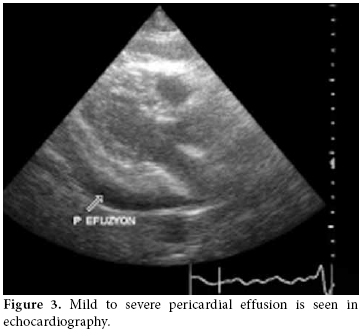

A 47-year-old female patient was admitted to the Yüzüncü Yıl University Faculty of Medicine cardiology clinic with complaints of shortness of breath and palpitations in August 2009. Medium to severe pericardial effusion was detected in an echocardiography examination. Suspecting cardiac tamponade, fluid was drained immediately and in the screening for pericardial effusion, leukocytosis (7200 leukosytes per mm. cub.) was determined. With the diagnosis of pericarditis, ceftriaxone and ciprofloxacin were started. However, no bacterial reproduction was seen in the patient᾿s pericardial fluid or blood cultures. This appeared to be on account of pericarditis due to rheumatoid arthritis. The patient was conscious and cooperative. She had complaints of widespread joint pain, chest pain, shortness of breath, and palpitations. Three weeks after starting sulphasalazine treatment for fever, the patient developed a swollen nose and cheeks along with erythema on her back. These findings were followed by increased skin complaints when exposed to sunshine. Shortness of breath and palpitations developed afterward. An examination revealed pain, swelling, and increased temperature in the carpometacarpal and metacarpophalangeal joints along with a limitation of motion in the left knee. Ulnar deviation and swan-neck deformity were detected in both hands. Tests revealed a blood pressure of 90/60 mmHg and a cardiac pulse rate of 120/min. and a body core fever of 37 centigrate. In a laboratory examination, the following was discovered: leukocyte count 18000, Hgb: 11.5 g/dl, platelets: 365.000, erythrocyte sedimentation rate (ESR): 34 mm/hour, CRP: 18.5 mg/dl, GGT: 283 U/L (5-31), ALT: 40 U/L (0-31), AST 35 U/L (0-31), LDH: 730 U/L (240-480), RF: 141 IU/mL, and anti-CCP was found to be positive.

In high resolution computed tomography (HRCT) there was linear atelectasis, and fibrotic changes were found which were more pronounced in the upper lobes of both lungs (figure 2). Mild to severe pericardial effusion was seen in echocardiography (ECHO; figure 3). Three days after 20 mg intravenous prednisolone therapy, fluid accumulation was considered to be gradually decreasing in ECHO (figure 4).